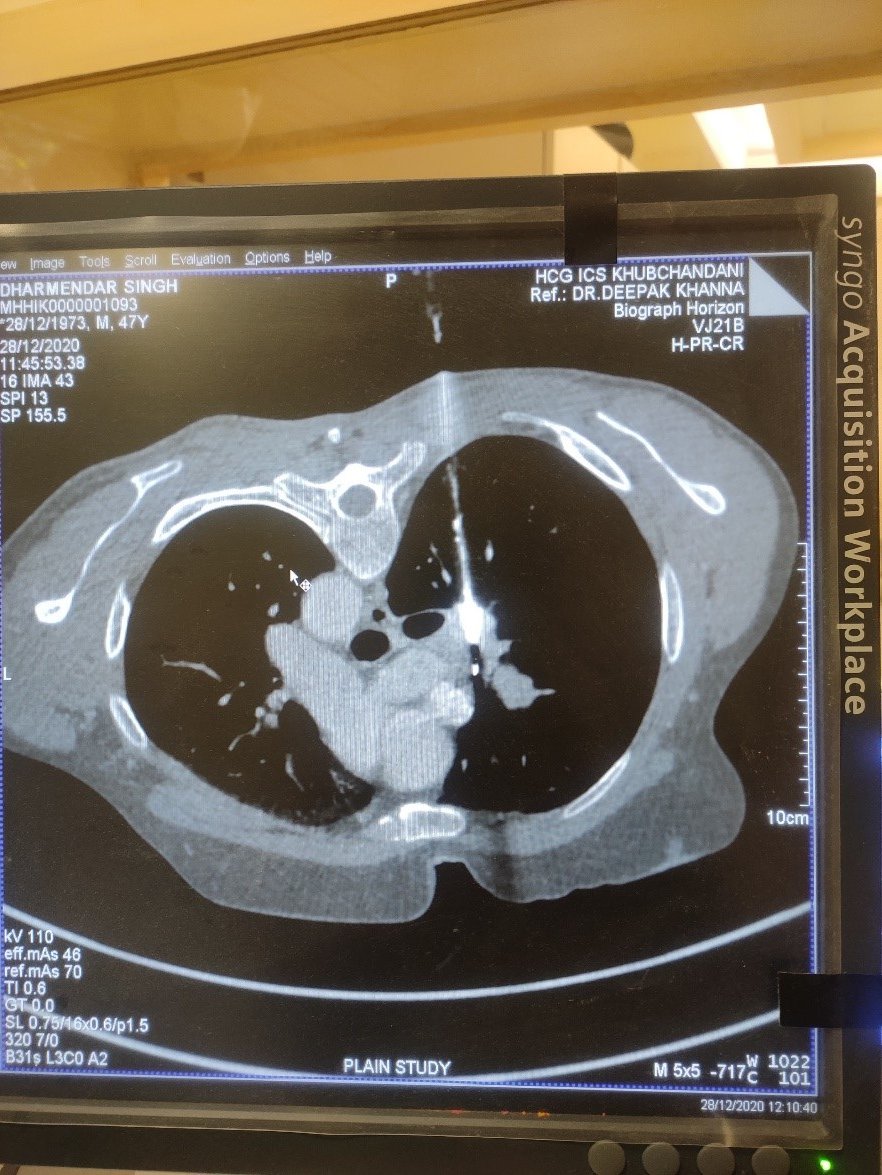

CT guided biopsy of Lung Mass/ Metastasis